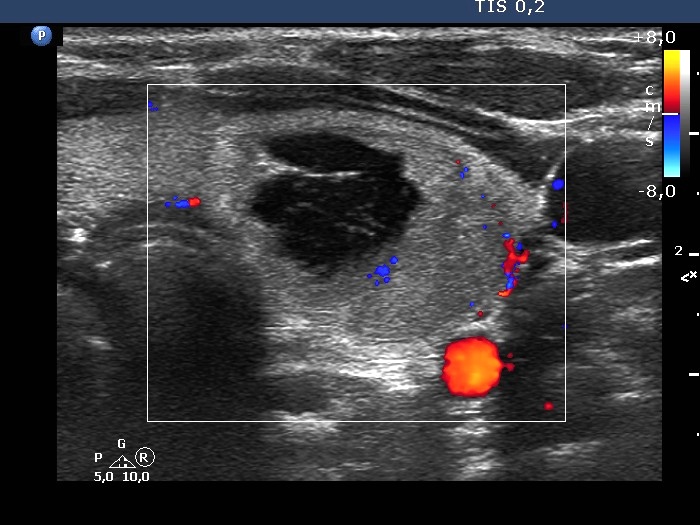

First examination (first row of images):

Ultrasonography. The thyroid was echonormal. There was a central-type cystic lesion in the left lobe. The cystic part presented numerous echogenic granules without a tail.We aspirated 5 mL bloody fluid. Aspiration cytology resulted in non-diagnostic cystic lesion.